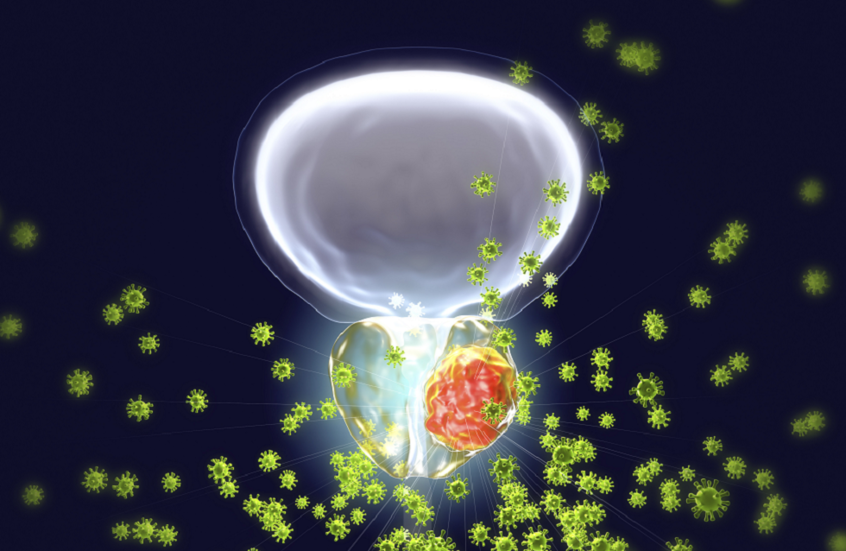

أظهرت دراسة جديدة أن التعرض لتلوث الهواء قد يزيد خطر إصابة الرجال بسرطان البروستات، خاصة أولئك الذين يعيشون في مناطق مكتظة بالسكان أو بالقرب من الطرق الرئيسية داخل المدن.

واستندت الدراسة إلى بيانات 224 ألف رجل في بريطانيا، بمتوسط عمر 58 عاما، تمت متابعتهم لمدة 13.7 عاما. وأظهرت النتائج أن من تعرضوا لمستويات أعلى من التلوث كانوا أكثر عرضة للإصابة بسرطان البروستات بنسبة 6.9% مقارنة بمن لم يتعرضوا له، مع زيادة الخطر مع ارتفاع مستوى التعرض.

وتركزت معظم الدراسات السابقة على الجسيمات الدقيقة PM2.5، التي يمكن استنشاقها بعمق في الرئتين، وتنطلق من مصادر مثل عوادم السيارات والانبعاثات الصناعية والزراعية واحتراق الوقود المنزلي. أما الدراسة الجديدة فقد درست تأثير خمسة من المكونات الرئيسية لهذه الجسيمات، بما في ذلك NO₃، ووجدت أنه الأكثر تأثيرا على خطر الإصابة.